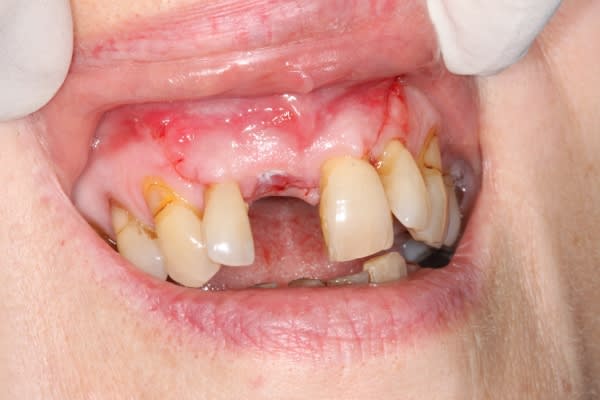

Un cas qui ressemble mais avec un implant qui n'est pas à l'intérieur du boitier osseux mais reconstitution de la paroi vestibulaire après pose d'un implant sur crête mince avec expansion, fissuration de la corticale vestibulaire.

Effondrement tissulaire après extraction et lambeau repositionné coronairement pour essayer de retrouver une papille entre centrale et latérale. La dent de la patiente est recollée.

La technique est bonne pour moi parce que les résultats sont constants en terme de reconstruction horizontale mais pas en verticale.